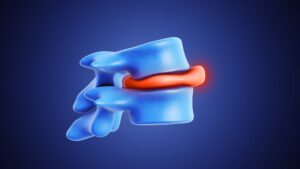

How Can I Check My Disc Bulge At Home?

A disc bulge occurs when a spinal disc extends beyond its normal boundary, sometimes pressing on nearby nerves. While imaging tests like MRI are needed

A disc bulge occurs when a spinal disc extends beyond its normal boundary, sometimes pressing on nearby nerves. While imaging tests like MRI are needed

A bulging disc occurs when the outer layer of a spinal disc weakens, allowing the inner material to protrude. Recovery time varies widely depending on

Spinal decompression can relieve pressure on discs and nerves and improve mobility. While gentle decompression is safe and beneficial, overdoing it can cause serious complications